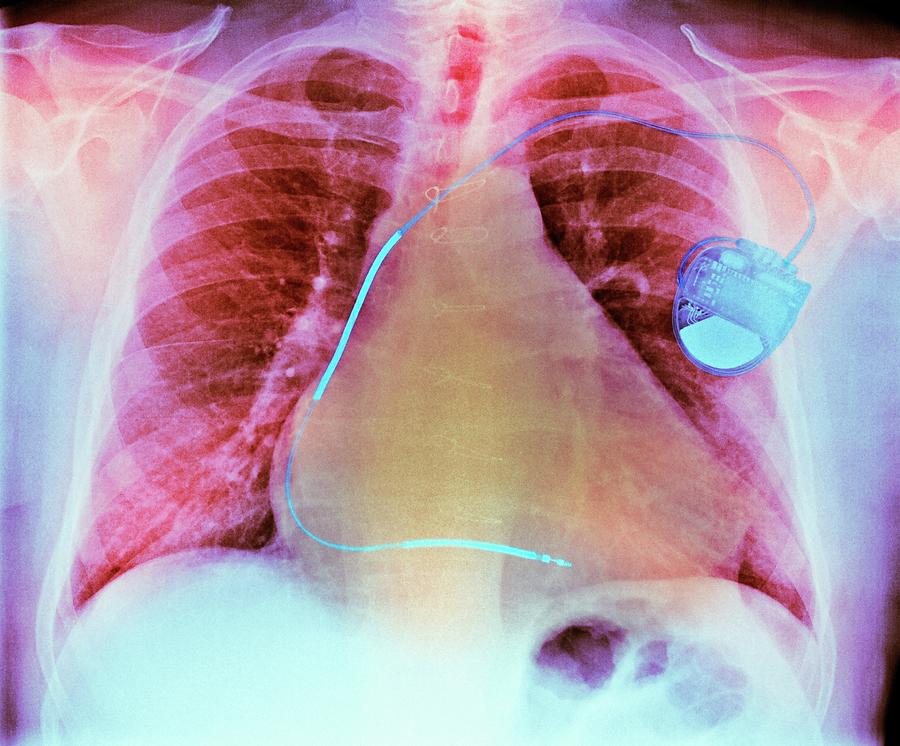

from pixels.com

Pacemaker For Heart Failure Photograph by Zephyr/science Photo Library